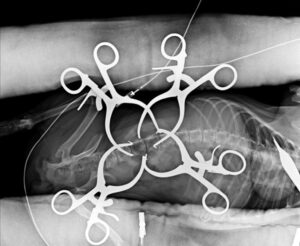

手術の様子です。骨髄移植も併用しました。時間がかかりましたが順調に回復し歩けるようになりました。良かったです。